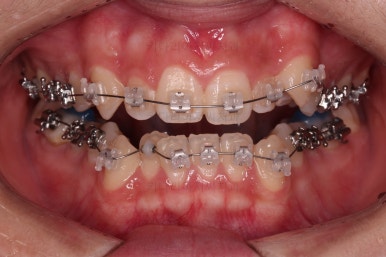

처음 장치를 부착한 모습인데요.

이번 환자분이 부산옥니교정에 사용한 장치는 엠파워 클리어라고 하는 자가결찰 세라믹 장치였습니다.

철사를 잡아주는 캡(결찰)이 브라켓에 달려있어 스스로 묶고 풀고가 가능한(자가) 세라믹 재질의 장치라는 뜻인데요.

대표적으로는 엠파워 클리어, 클리피씨 등이 있습니다.